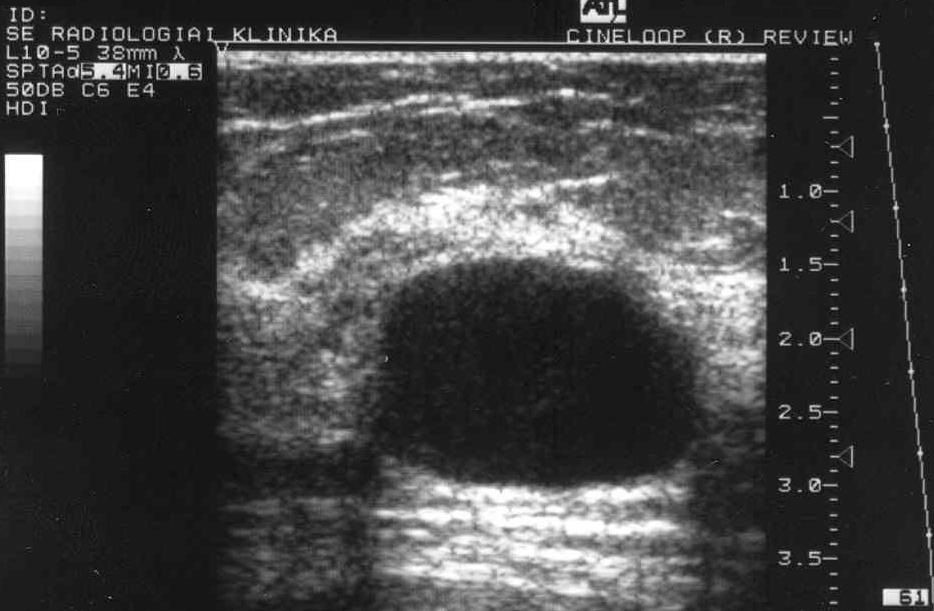

- Relatív hangfelerősödés:

Éles kontúrú cystosus képlet mögött, sávban jelentkező hangfelerősödés (pl. nagyobb emlő-cysta mögötti területen) (17. ábra).

Image

17. ábra: Nagy emlőcysta UH, mögöttes hang felerősödés